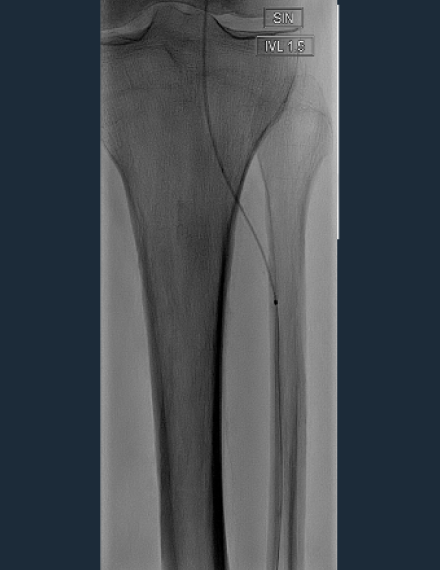

Shockwave Javelin Treatment

After crossing with a 0.014 guidewire, 2.0 mm percutaneous transluminal angioplasty (PTA) balloon couldn’t cross at the origin of the ATA. Shockwave Javelin Peripheral was used to modify the calcium and cross the occlusion. -

120 pulses were delivered along the proximal and medial segment of the ATA. Shockwave Javelin Peripheral allowed to modify calcium along the lesion, enabling effective treatment with 2.5 mm PTA balloon. -